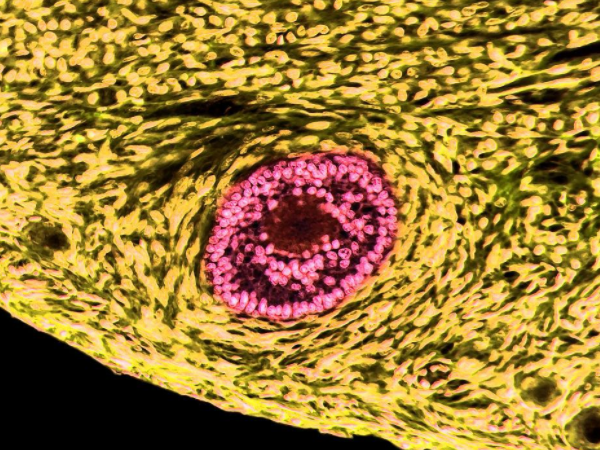

卵泡生长速度是有一定的标准的,一般在月经结束的3-5天卵泡会出现,然后不断发育,此时只有1.5-1.9mm,而月经的10-12天,此时卵泡会发育到12-15mm,到月经14天左右则会发育到18-25mm,女性可以根据发育的速度判断卵泡发育情况。卵泡生长速度对照表卵泡就是卵子的“前身”,是由卵巢排出来的,是有卵母细胞及其小型的卵泡细胞组成。其中卵泡的成长:分为原始卵泡、生长卵泡和成熟卵泡,在一个月内...